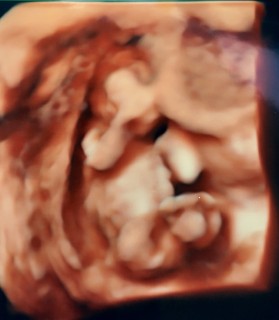

4Dエコーもやってもらい、いい感じにぐねぐね動いてくれたので色んな角度からみれました!

4Dエコーに感動しました(°ω°)! 赤ちゃんは8センチ位でいっちょ前に足組しているようにみえ、シェーのポーズにも見えます。次回4週間後で性別聞けたら買い物楽しみです(*´ω`*)

赤ちゃんの形になっててびっくり! とっても愛おしくなりました。